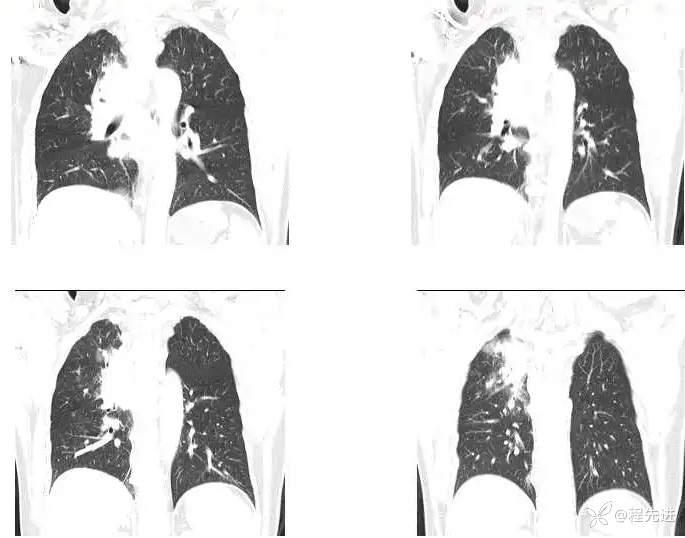

主 诉:间断咳嗽、痰中带血1月,发现肺门占位8天

现病史:患者1月前受凉后出现咳嗽咳痰,痰中见血丝,量少,伴有右侧胸痛不适,夜间有盗汗,无发热,在社区予以抗感染治疗3天(具体用药不详),胸痛症状缓解,但仍间断出现痰中带血,未再行诊治;8天前检查发现肺门占位;患者近2日咯血量较前增多,每日约4-5口,为鲜红色

CT增强:

MR平扫+增强: